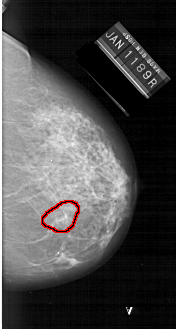

A_1230_1.RIGHT_MLO

RIGHT_CC LINES 6241 PIXELS_PER_LINE 3331 BITS_PER_PIXEL 12 RESOLUTION 43.5 OVERLAY

FILE: A_1230_1.RIGHT_CC.OVERLAY

TOTAL_ABNORMALITIES 1

ABNORMALITY 1

LESION_TYPE MASS SHAPE ARCHITECTURAL_DISTORTION MARGINS ILL_DEFINED

ASSESSMENT 4

SUBTLETY 1

PATHOLOGY MALIGNANT

TOTAL_OUTLINES 1

BOUNDARY